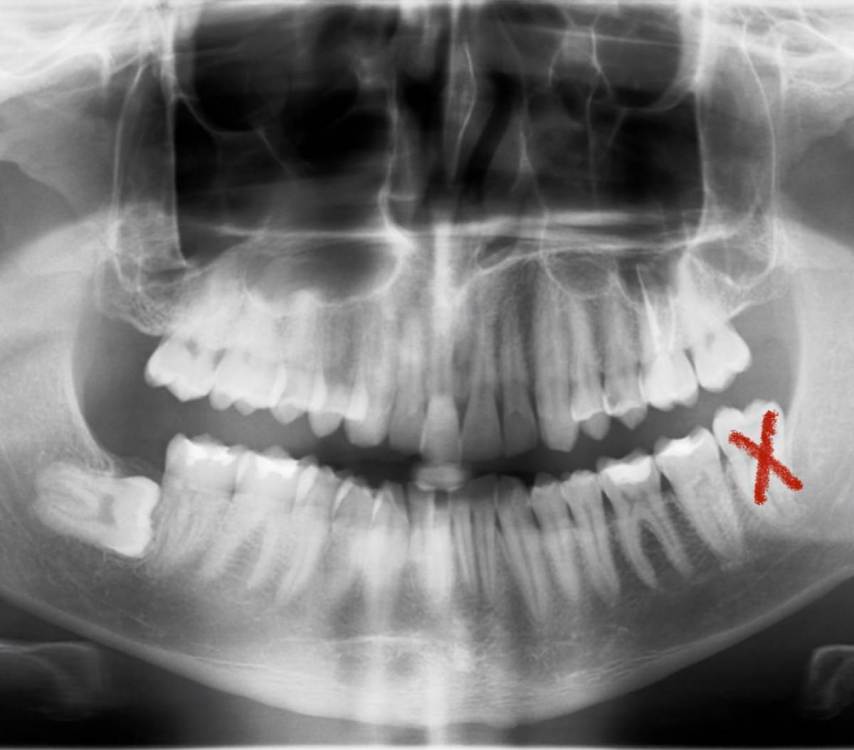

sitnick Опубликовано 20 июля, 2022 Поделиться Опубликовано 20 июля, 2022 (изменено) Добрый день! Мне 30 лет. Подскажите пожалуйста, планирую поставить брекеты, ортодонт настоятельно порекомендовала перед этим вырвать все восьмерки, вылечил все зубы, где надо поставил пломбы, удалил 3 восьмерки, осталась одна снизу слева. При осмотре снимка врач-стоматолог сказал, что случай не простой и порекомедовал не трогать зуб из-за близкого расположения к лицевому нерву, если не беспокоит. Хотелось бы услышать мнения специалистов по данному типу ретинированных зубов, стоит ли от них избавляться, высокий ли риск повреждения нерва, зуб сейчас не беспокоит, но может ли такой зуб начать движение в будущем и насколько менее травматичным является использование лазера в данном случае вместо скальпеля. Второй вопрос к ортодонтам по брекет-системам. Бюджет устраивает любой, хотелось бы узнать какие брекет системы эффективнее исправляют глубокий прикус. Может ли invisalign исправить скученность зубов и раздвинуть семерки? Так же щелкает челюсть с одной стороны при приеме пищи, как это можно исправить? К сожалению, не обладаю большим количеством свободного времени, много заграничных командировок, поэтому, приходится задавать вопросы удаленно Изменено 20 июля, 2022 пользователем sitnick Ссылка на комментарий

It'sGeorgy Опубликовано 20 июля, 2022 Поделиться Опубликовано 20 июля, 2022 Добрый день. Нужно КТ. У вас панорамный снимок, по нему невозможно точно оценить близость корней к нерву. 1 Ссылка на комментарий

kramer Опубликовано 20 июля, 2022 Поделиться Опубликовано 20 июля, 2022 Удаляйте и не бойтесь, риск есть всегда, но в вашем случае зуб от нерва относительно далеко 1 Ссылка на комментарий